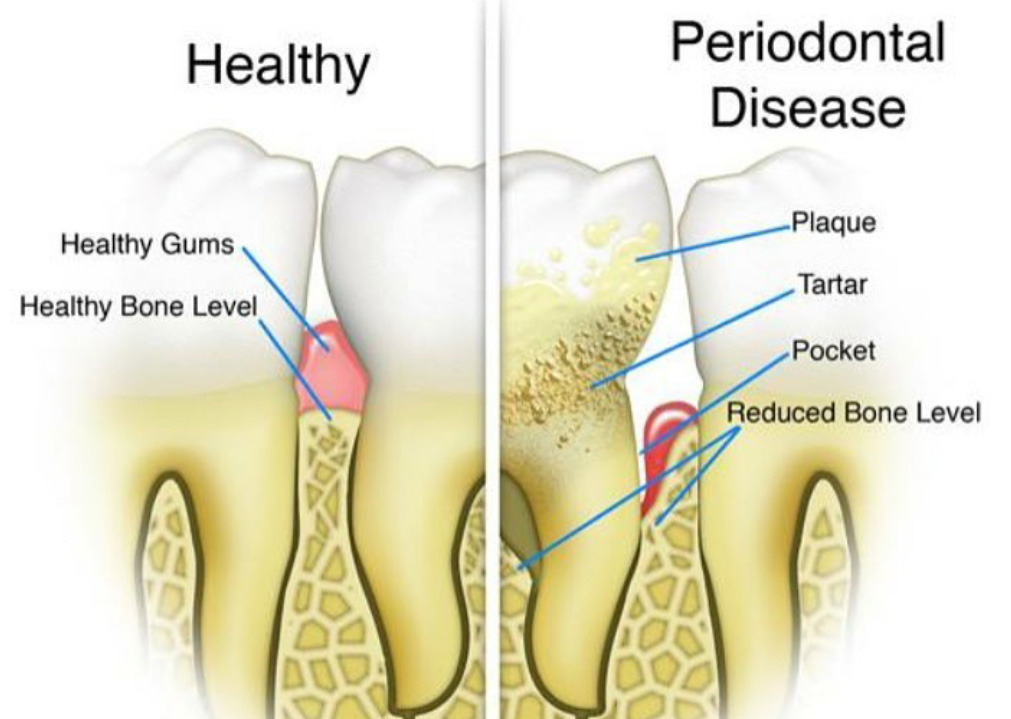

Receeding gums, Inflamed Bleeding Gums, Loose Teeth are treated by Scaling and Flap surgeries…